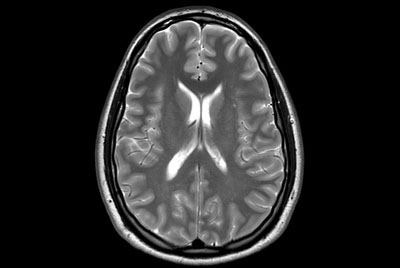

Brain - White matter lesions